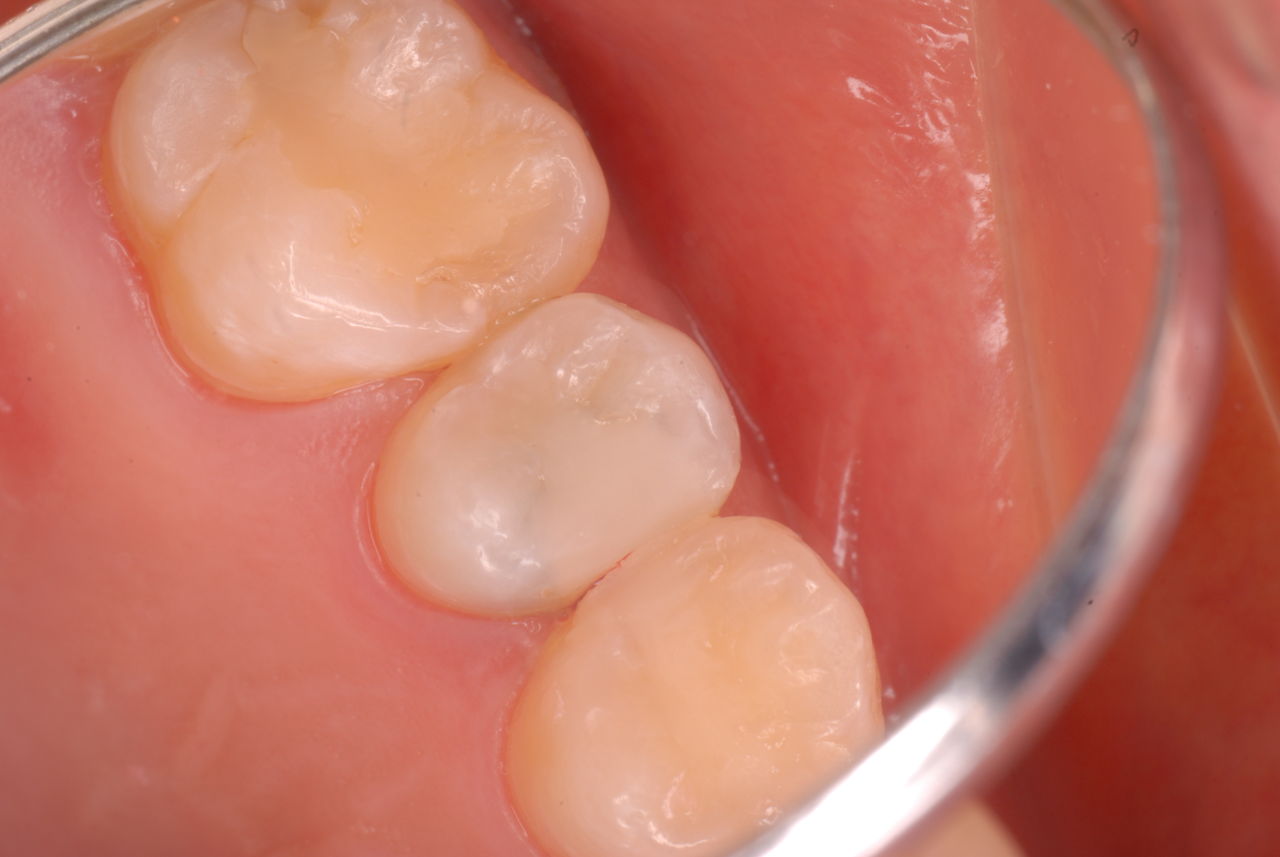

歯周病になっていましたが、少し色が黄色くなっているだけで比較的綺麗な歯の状態です。

平成9年来院神経を取り、同時に歯周病の話をしてそのまま来なくなっていたかたですが、たまたま一部欠けてきました。それで来院。